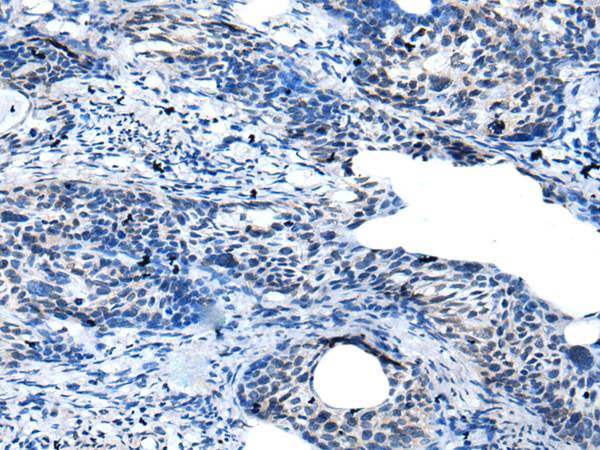

分类: 科研抗体货号: P12706别名: KHL4; DKELCHL应用: IHC反应种属: Human

分类: 科研抗体货号: P12738别名: G2L3应用: IHC反应种属: Human

分类: 科研抗体货号: P12733别名: GAS应用: IHC反应种属: Human, Mouse, Rat

分类: 科研抗体货号: P12752别名: PYHIN2; IFNGIP1应用: IHC反应种属: Human